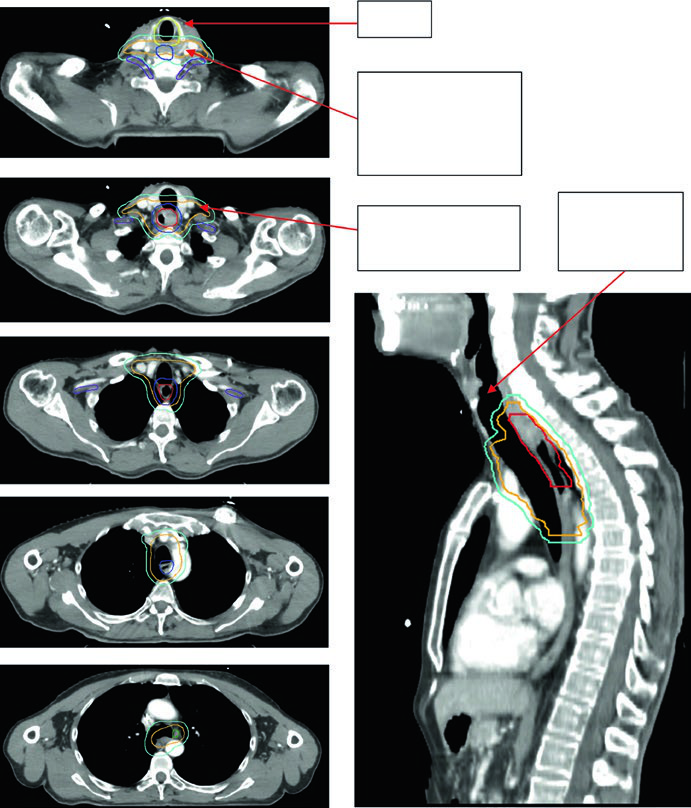

Case 1: Cervical/Upper Thoracic SCC — 69-Year-Old

A 69-year-old patient with SCC of the cervical/upper thoracic esophagus. PET-CT revealed FDG-avid primary and mildly avid paratracheal lymph nodes. EGD showed an ulcerating submucosal mass 15–23 cm from the incisors. Delineated volumes included: brachial plexus (purple), larynx (yellow), esophageal GTV (red), nodal GTV (green), CTV (orange), PTV 54 Gy (cyan), and PTV 60 Gy (dark blue). The superior border of the supraclavicular field was placed at the inferior border of the cricoid cartilage, with bilateral elective SCV nodal coverage.